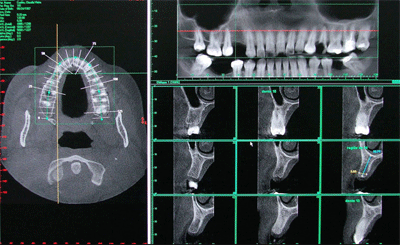

A Tomografia Computadorizada da Raio-X Mangabeiras possui a mais avançada técnica de aquisição volumétrica na odontologia e é uma importante ferramenta para o planejamento de procedimentos odontológicos, principalmente para o tratamentos com implantes, além de apresentar uma abordagem sistemática dos transtornos orais e das articulações da região da boca.